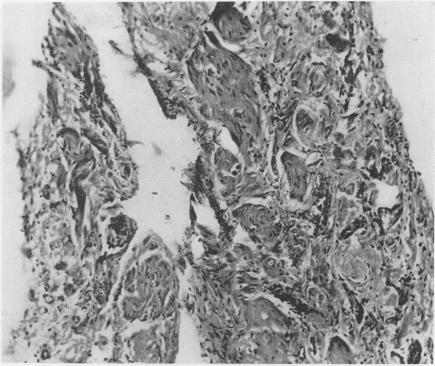

Congenital cysts of the mesentery; report of four cases.

Ann Surg. 1957 Mar;145(3):428-36. doi: 10.1097/00000658-195703000-00020.